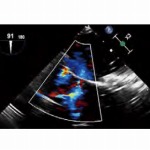

「HEARTROID」は、心臓カテーテル検査・治療に携わる医療従事者向けのトレーニングシステムです。

3Dプリンターで再現された透明な心臓モデルと拍動ポンプを使うことによって、X栓透視下ならびにカメラビューでの実践的でハイレベルなシミュレーションが可能になります。これから心臓カテーテルを始める若い先生方や、大学病院における医学生の教育はもちろん、経験あるオペレーターの先生が手技の検証や確認を行うのに最適です。